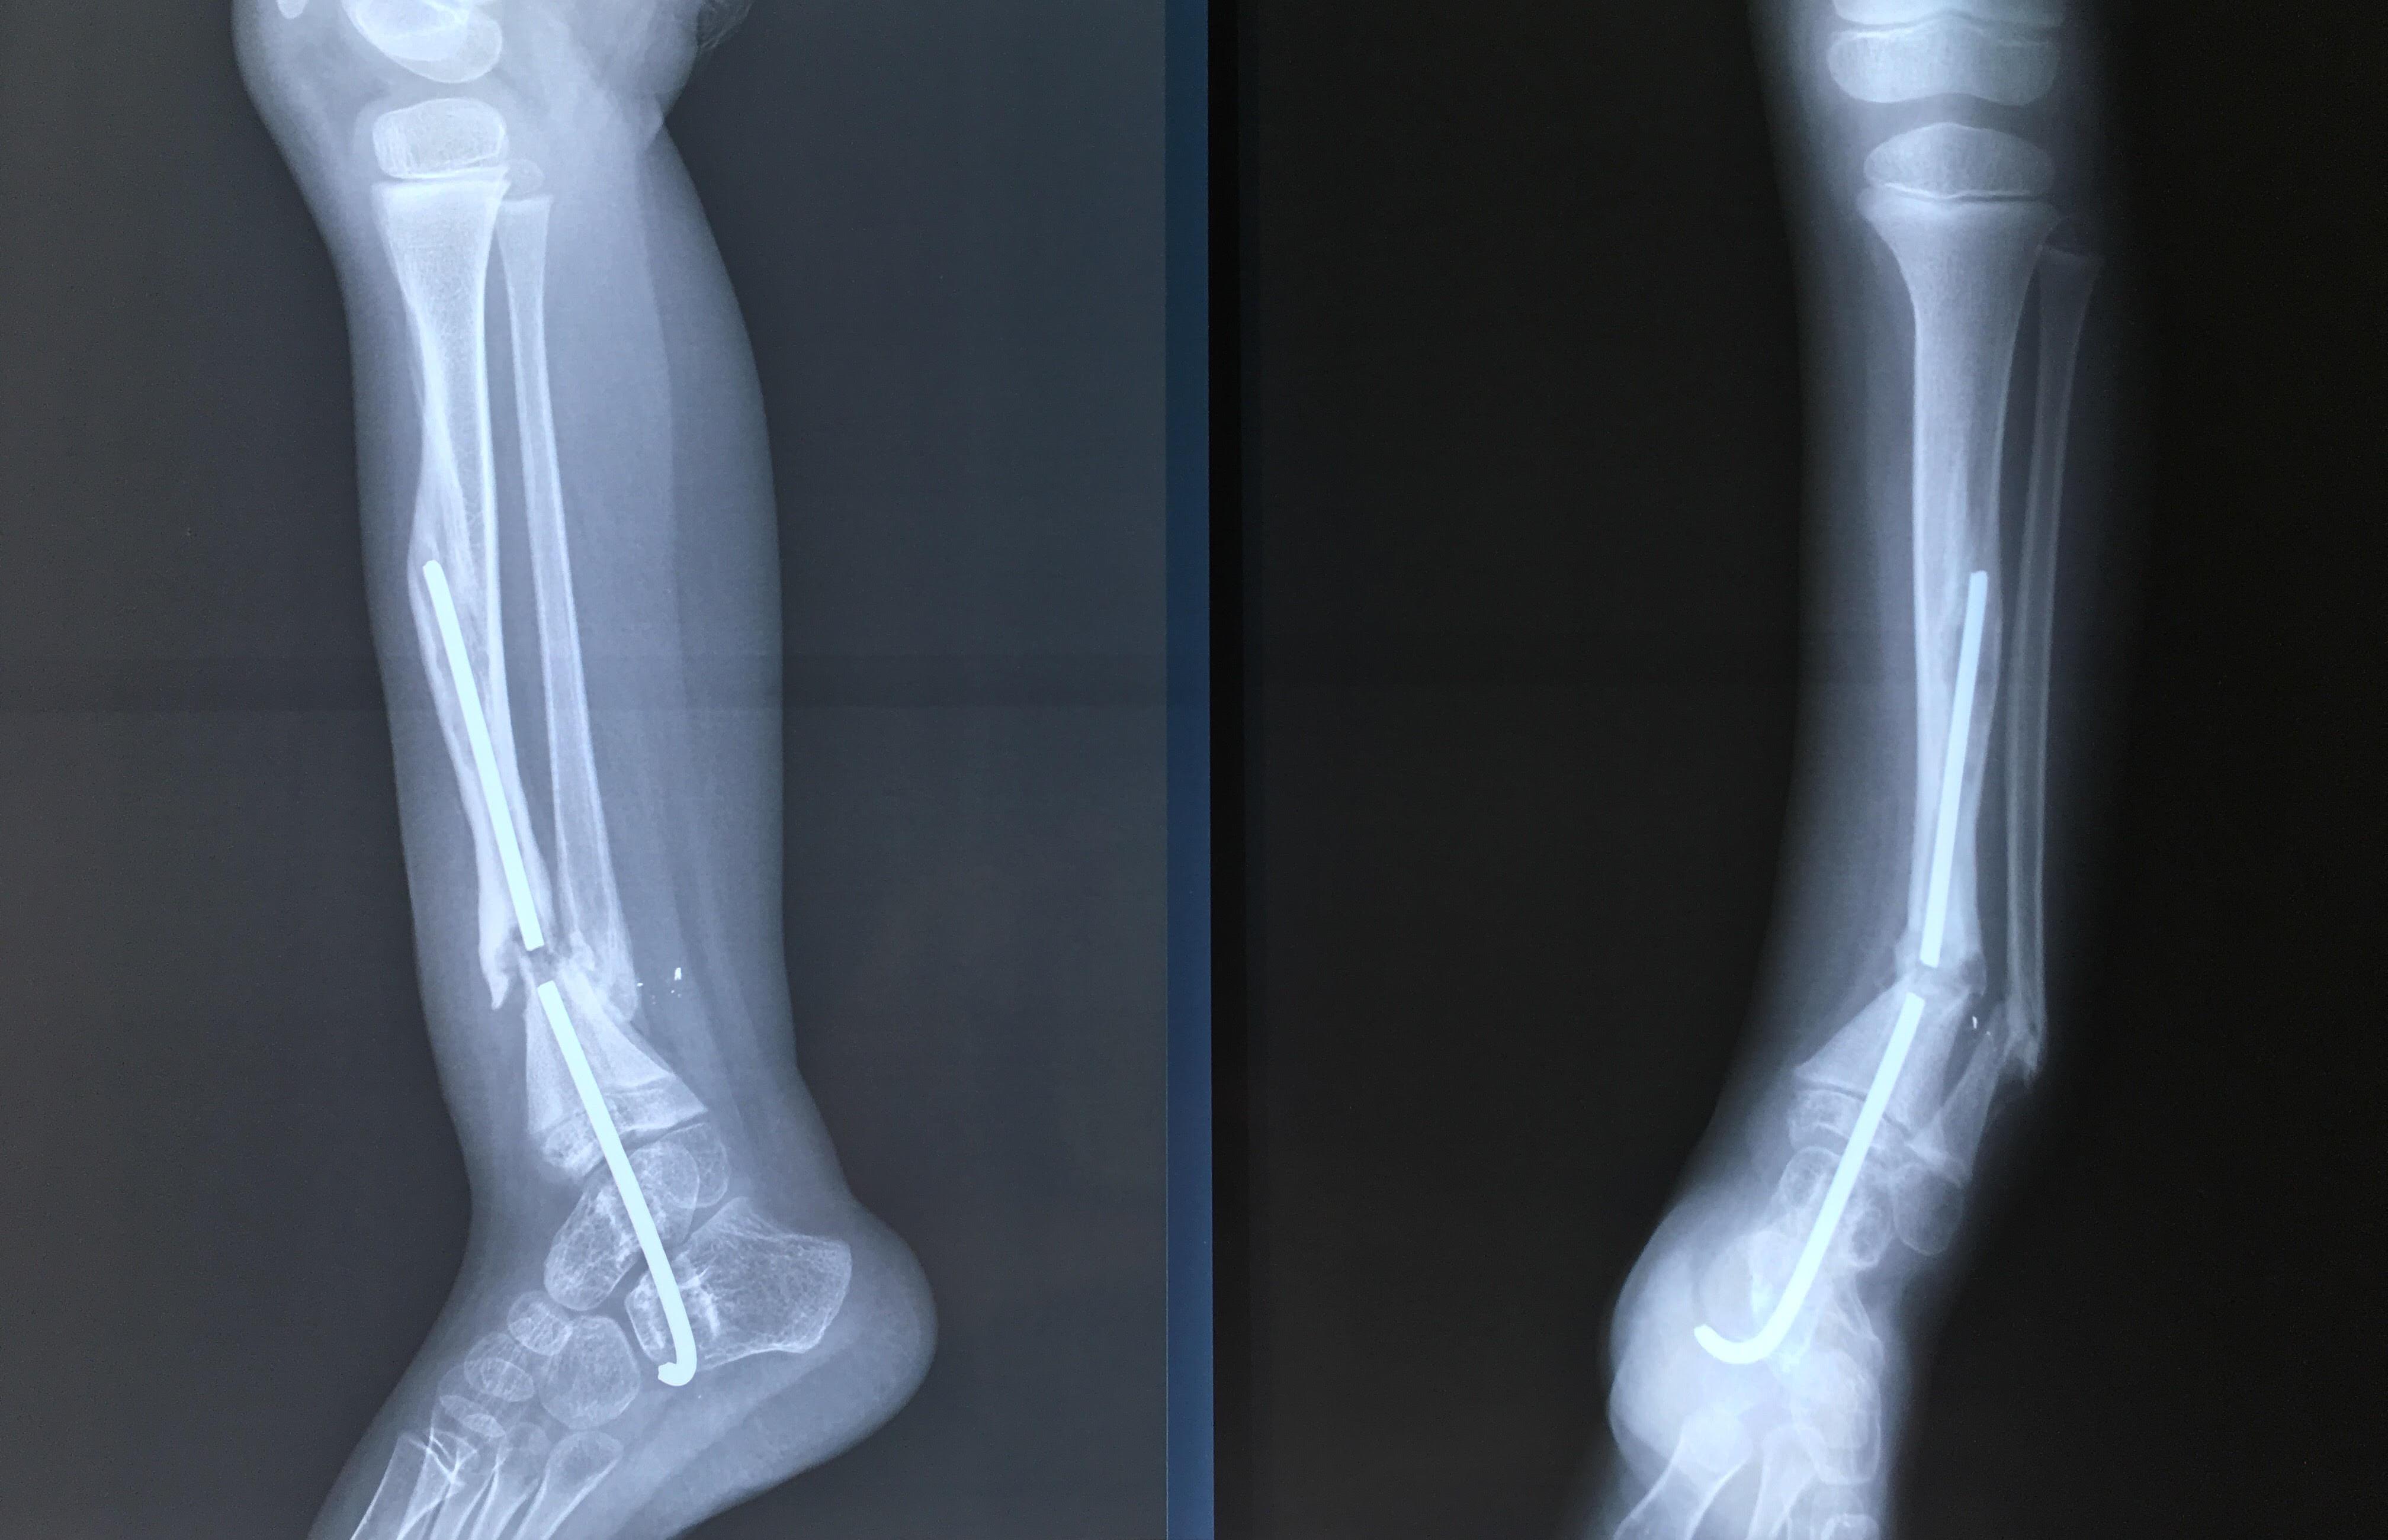

Phẫu thuật thành công ca bệnh hiếm gặp...khớp giả bẩm sinh xương chày

26/06/2019 17:00

Đã xem: 3523

Bệnh viện Chấn thương- Chỉnh hình Nghệ An, vừa phẫu thuật thành công cho bệnh nhi khớp giả bẩm sinh xương chày